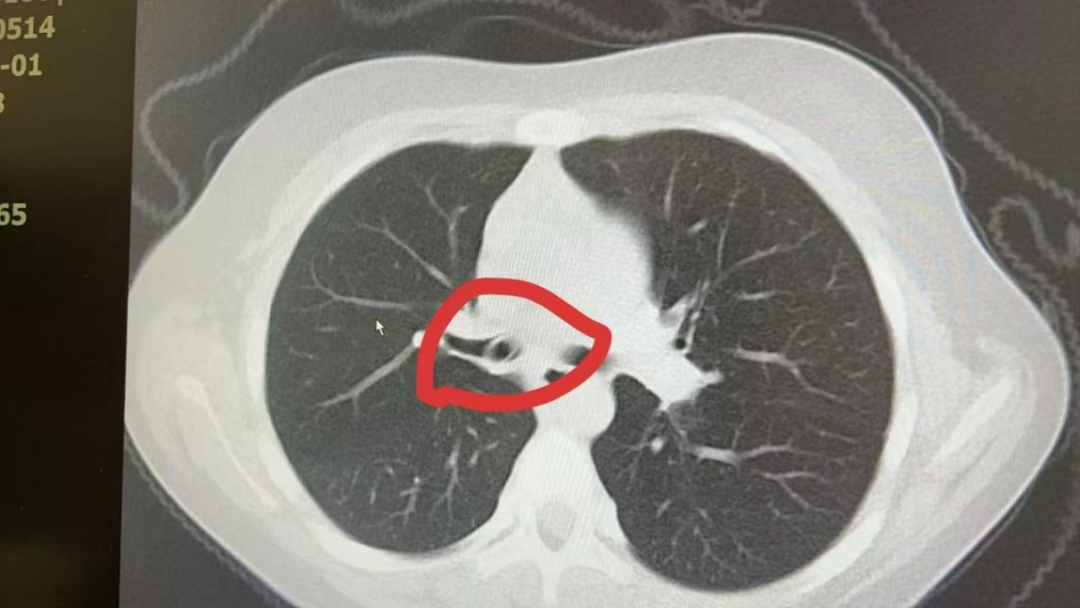

刘艳丽继续耐心地询问家长得知,妮妮在5天前确实有过一次用嘴叼着笔玩的情况,并且出现呛咳,家长发现后当即为她实施了海姆立克法,很快,呛咳症状消失,但是发现妮妮手中圆珠笔的前端笔嘴不见了!随后家长带她到当地医院就诊,经过检查没有在口腔和咽喉部发现笔嘴,加之孩子没有明显其他症状,家长也就放心了。没多久,妮妮就出现了咳嗽和喘息的症状,家长还以为是患上了支原体肺炎。听闻这一情况,刘艳丽当即为孩子安排了快速胸部CT检查,这一查,真相大白了。

CT影像

经过反复查看影像资料,发现丢失的笔嘴就在孩子的右主支气管内。刘艳丽和儿内科周士英副主任医师共同认为,笔嘴较大,并且在气道内嵌合紧密,需做好充分的手术预案和应急措施。随后,刘艳丽联系了麻醉科和内镜中心,相关人员经过充分术前讨论和准备,于1月2号上午9点,在喉罩麻醉下,儿内科支气管镜小组刘艳丽、周士英,孙丽伟、高辉香医师及麻醉科赵德君主治医师,内镜中心护士长李小娜、张瑞兆护师共同为妮妮进行了支气管镜探查及异物取出术。得益于术前的准备充分,操作人员使用直径2毫米异物钳、从笔嘴下面2毫米左右的缝隙入手,将坎顿紧密、几乎不留缝隙的笔嘴完整取出,整个操作过程不到10分钟!经过测量,笔嘴竟长达2.5cm,最宽处直径1cm。